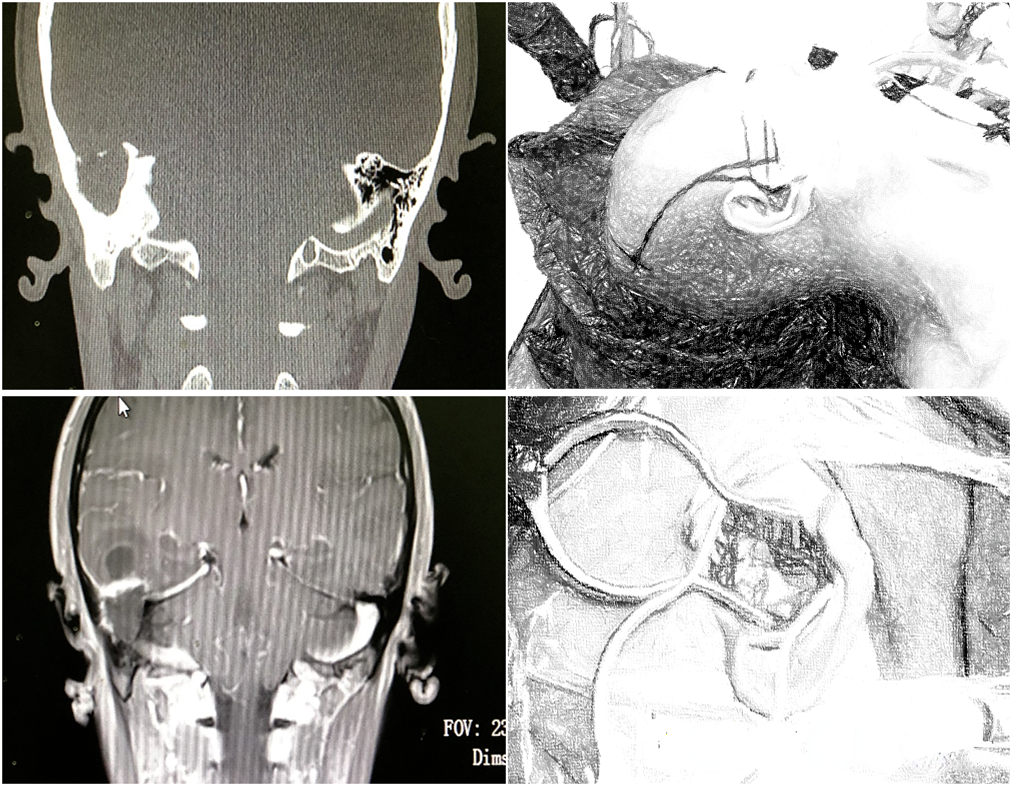

2022.03.02 MR/CT:左侧额叶脓肿形成,直径4cm,颞叶小脓肿,直径约1CM。蝶窦内局限性积液,左侧眼眶内组织肿胀,考虑脓肿形成。可见脓肿与前颅底薄弱部位关系密切。

非功能区脑脓肿是否手术治疗,一般根据脓肿直径,一般认为直径>3cm者,需要手术引流或切除。患者额叶脓肿直径为4cm,占位明显,手术指征明确;但其源于鼻窦,及眼眶内感染,必须同时处理,否则颅内脓肿必将死灰复燃。而脓肿能够波及颅内,说明颅底骨质薄弱或有所缺损,从患者影像上也能够证实这一点。

2022.03.04 次冠状入路额叶脓肿切除+前颅底修补术

遂于3月4日,在双镜联合下行额叶脓肿切除及眶内脓肿引流术。上图可见额叶脓肿切除后,前颅底薄弱区域,以额部骨膜瓣翻折进行修补。

2022.03.04同期鼻内镜下视神经管减压+眶内脓肿切开引流术

可见首次手术鼻窦开放充分,引流效果好。但视神经管及眶壁骨质大部完整,眶骨膜完好,切开眶骨膜,方见脓肿。说明首次手术并未开放眼眶及视神经管,导致引流不畅,治疗效果不佳。术后患者恢复良好,随访期间,眼球凸出逐渐恢复,但视力无明显改善。